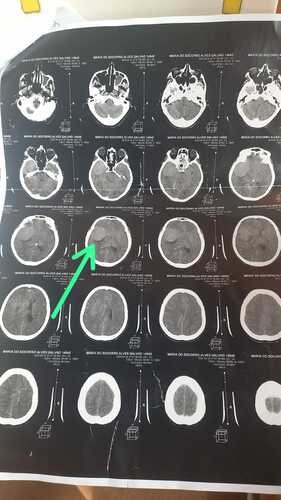

Recentemente, Maria do Socorro recebeu o diagnóstico devastador de um tumor na cabeça. Esta notícia abalou não só ela, mas todos nós que a amamos e admiramos. No entanto, Maria do Socorro é uma lutadora e está determinada a vencer esse tumor.

Para isso, ela precisa passar por uma cirurgia crucial. Esta cirurgia é sua melhor chance de vencer o tumor e recuperar sua saúde. No entanto, os custos associados a este procedimento são significativos, e é por isso que estamos lançando esta vaquinha online.